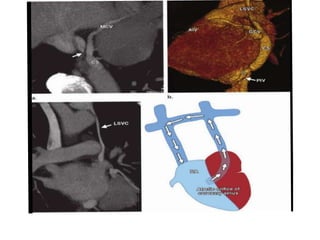

INFERIOR CAVAL VEIN

A. Absence of the Hepatic Segment of Inferior Caval

Vein With Azygos Continuation

This is the most common anomaly involving the inferior caval vein. It

exists because of the absence of the infrahepatic portion of the inferior

caval vein (INTERRUPTED IVC). The blood from the lower part of the body

reaches either the left or right superior caval vein via the dilated azygos

venous system

Hepatic veins drain blood from Liver to Morphological RA

occurs dur to Abnormal development of right subcardinal vein which fails

to anastomose to right vitelline vein.

• Supracardinal venous system normally forms

Azygous vein which provides drainage to

developing superior caval vein

• INCIDENCE: 0.6%

• It is most relevant in the setting of patients

having functionally univentricular hearts who

are undergoing construction of a

cavopulmonary connection. The mere

connection of the superior caval vein to the

pulmonary arteries in this setting is equivalent

to a near total cavopulmonary connection. This

is so-called Kawashima repair